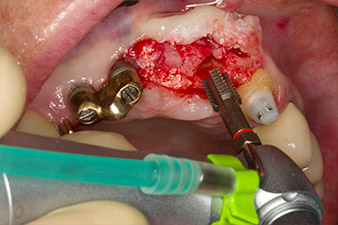

Nach primärer Abheilung werden die Weichgewebe mithilfe der basal unterfütterten Brücke ausgeformt. Zwei Monate später erfolgt die Freilegung mit einem leicht palatinal gelegten Kieferkammschnitt (Abb. 2).

Der Alveolarknochen erweist sich an Position 22 als ausreichend dimensioniert. Die Abbildungen 2 und 4 zeigen die Implantatbett-Aufbereitung, den Gewindeschnitt und die Implantation mit dem Implantmed.

Der neue Implantologiemotor wird jeweils mit den geeigneten chirurgischen Winkelstücken von W&H verwendet.